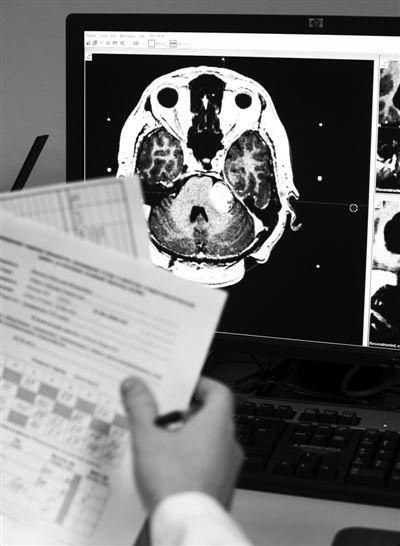

受害者的急诊ct报告(图片来自京华时报微博)

患者病情,病史,体征,影像学检查等确诊为颅内肿瘤导致的三叉神经痛

脑肿瘤核磁报告单图片

脑瘤核磁共振图片